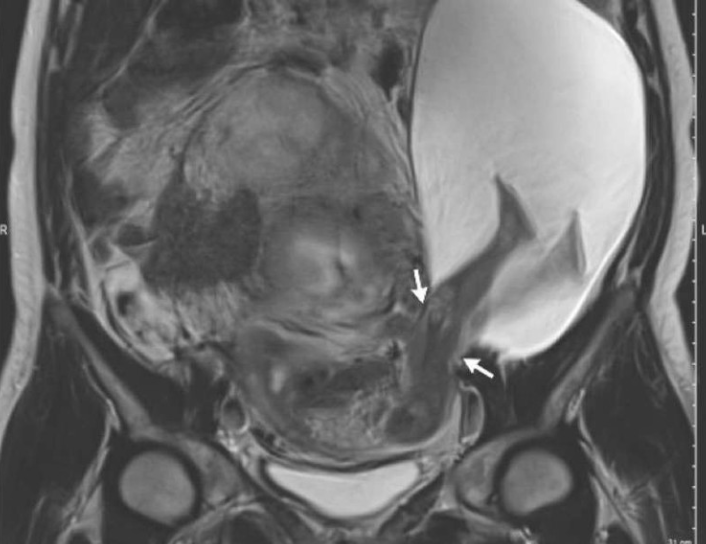

Un caso que asombró a médicos y medios ocurrió en 2017, en China. Una mujer embarazada de 35 semanas sufrió una ruptura uterina causada por una patada de su bebé. La fuerza del movimiento del feto fue suficiente para abrir una brecha de aproximadamente 7 centímetros en el útero, un hecho que parecía imposible, pero que realmente ocurrió.

¿Por qué ocurrió algo así? Resulta que la mujer había tenido una cirugía previa para extirpar un fibroma uterino. Los especialistas explican que, al no esperar el tiempo recomendado antes de concebir nuevamente, la cicatriz en el útero no estaba lo suficientemente fuerte para resistir movimientos muy bruscos del bebé, lo que terminó en la ruptura.